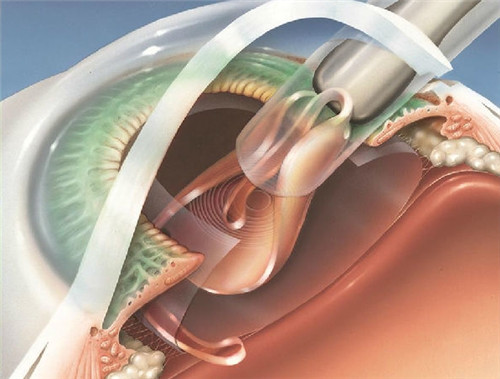

三焦点晶体:相比传统单焦点,可同时优化远、中、近视力,术后不用戴老花镜。

个性化方案:根据患者角膜状况、用眼习惯定制手术,比如喜欢看书或开车的老人,医生会调整晶体参数优化视觉结果。

65岁的张阿姨去年在普瑞做了三焦点晶体手术,术前她看手机要拿很远,出门还得戴老花镜。术后一周复查,远视力1.0,近视力0.8,现在买菜、看药瓶上的小字都没问题,甚至能重新穿针引线。

70岁的王爷爷有轻度白内障+老花,在华视做了三焦点晶体植入,术后第二天就看清楚远处车牌号,一周后能轻松读报纸。他说:“以前总怕手术风险大,但医生解释得很清楚,现在连夜间开车都不模糊了。”